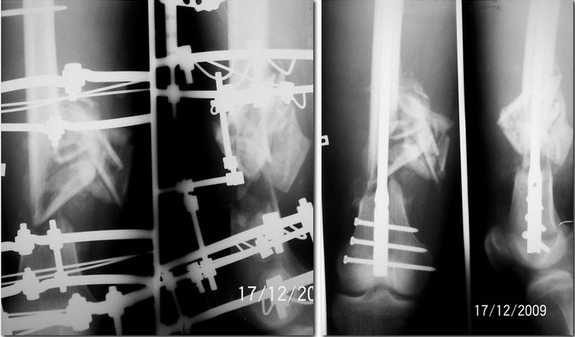

Прислушавшись к мнению уважаемых коллег провели двухэтапное лечение пациента. Пару дней

назад забили штифт, без укорочения, колено редрессировали до 90гр. Всем спасибо за дельные

советы.